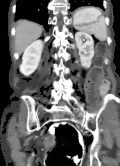

| Coronal CT of the abdomen, demonstrating a volvulus as indicated by twisting of the bowel stock | |

Coronal view of sigmoid volvulus with "whirlpool sign" -